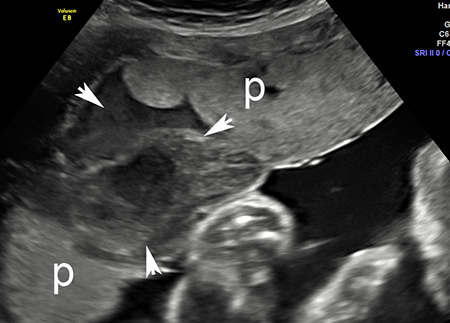

Imagem de ultrassonografia de descolamento da placenta: a placenta normal está marcada com 'p'; área de descolamento indicada por setas brancas

Do acervo de Dr Y Oyelese; usado com permissão